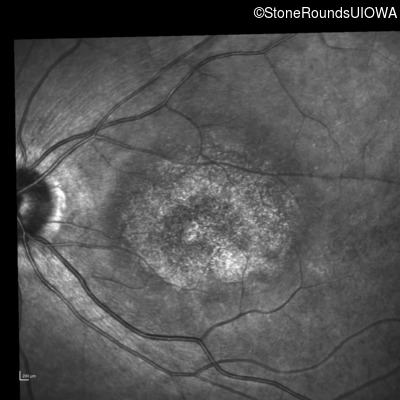

AR Stargardt Disease (IIA)

AR Stargardt Disease (IIA)

| Age at visit: 12 years |

| Age at visit: 13 years |

| Age at visit: 15 years |